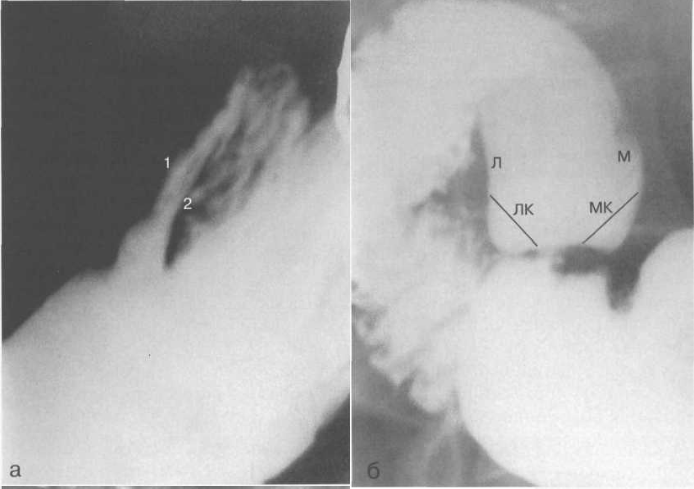

Рис. 11.35. Рентгенограммы луковицы двенадцатиперстной кишки.

а — в левой косой проекции:

1 — передняя стенка; 2 — задняя стенка; залуковичная часть двенадцатиперстной кишки.

б — в правой косой проекции:

Л — латеральный контур; ЛК — латеральный карман; М — медиальный контур; МК — медиальный карман.